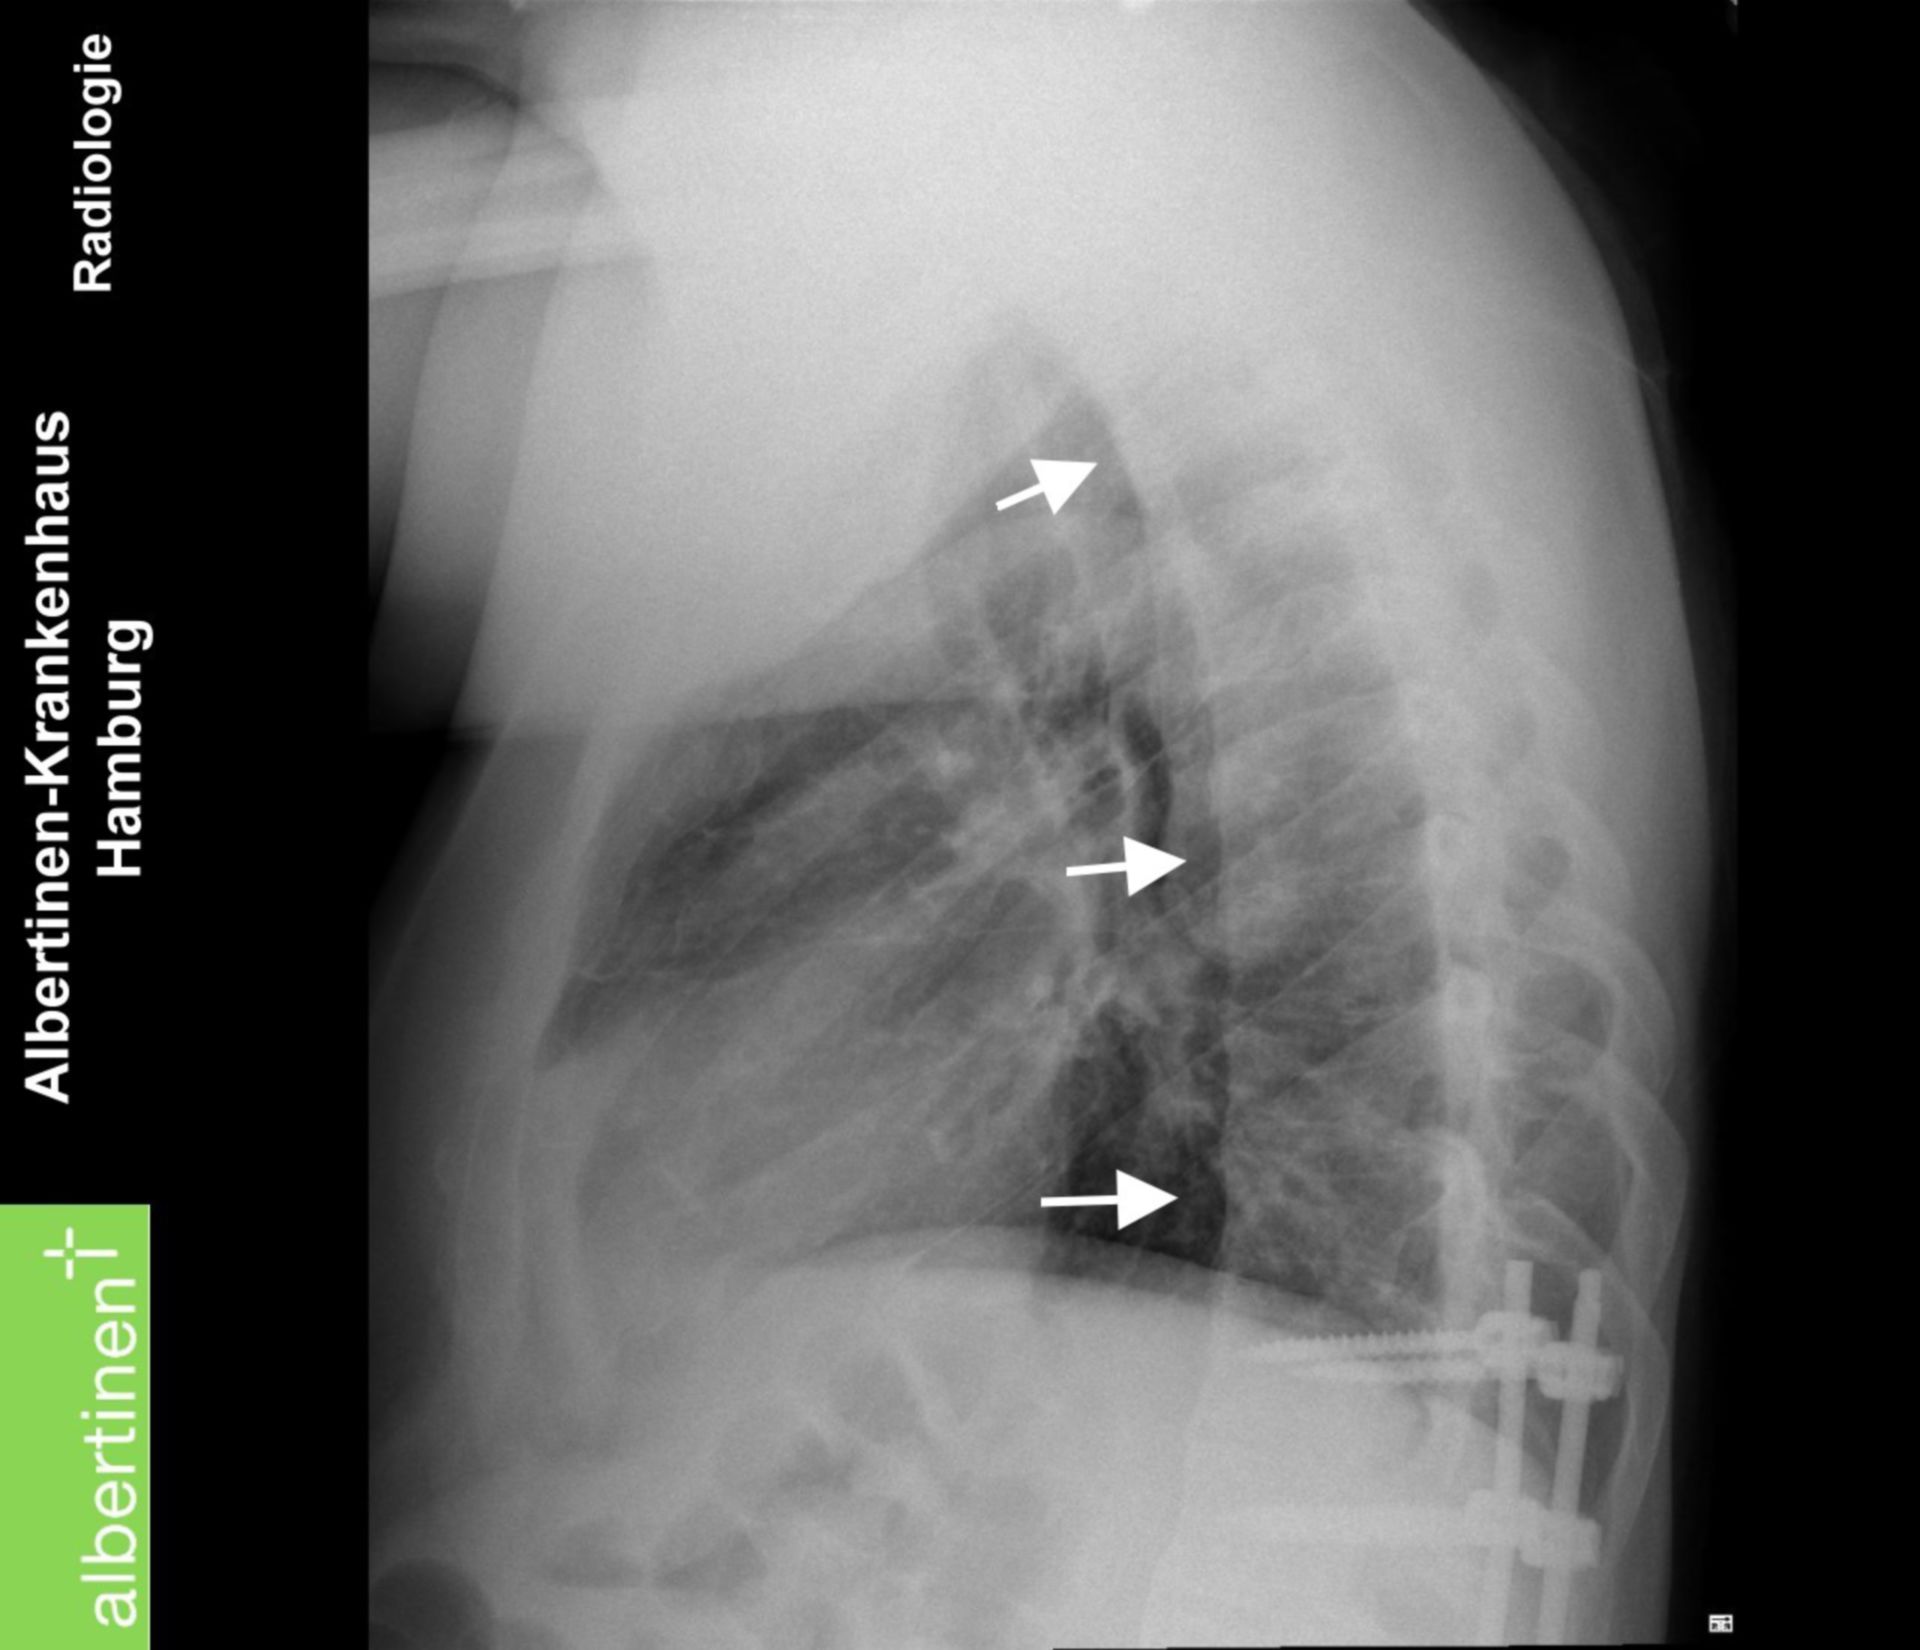

Boala Bechterew, cunoscută și sub denumirea de spondilită anchilozantă, este o afecțiune reumatismală cronică ce afectează în principal coloana vertebrală.

Aceasta se caracterizează prin inflamația articulațiilor sacroiliace (între bazin și coloana vertebrală) și a vertebrelor, care poate duce la o rigiditate și o mobilitate redusă a coloanei vertebrale.